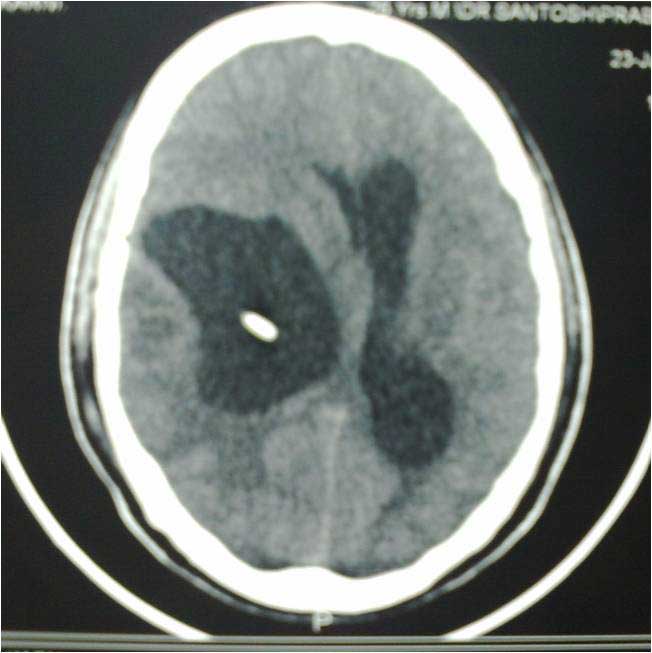

Brain Abscess Brain Abscess Post OP 2 Clinical Intra OP ,After Excising The Granuloma Intaop Scalp Abscess CT Scalp Abscess Cerebellar Abscess Post OP Clinical Cerebellar Abscess Brain TB Granuloma Post OP CT Scan Brain Infection Brain Abscess Preop MRI 2 Brain Abscess PRE OP Clinical 1 Brain Abscess PRE OP Brain Abscess Intraop 2 Brain Abscess Following Shunt Temporal Abscess T2W of TB Granuloma Scalp Abscess Preop CT Marking PRW OP MRI of TB Granuloma Post OP Clinical Photo Post OP Cerebellar Abscess Post OP Brain Abscess Intraop Specimen of Granuloma